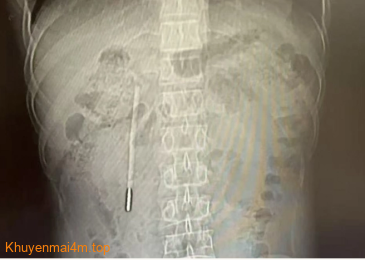

Truyền thông Trung Quốc đưa tin Wang đi khám do có triệu chứng đầy bụng, khó tiêu kéo dài. Kết quả chụp CT ổ bụng phát hiện một dị vật nằm ở tá tràng, được xác định là một chiếc nhiệt kế thủy ngân. Đầu nhọn của nhiệt kế đã tì sát vào thành ruột, có thể gây thủng ruột hoặc xuất huyết ồ ạt bất cứ lúc nào.

Phim chụp cho thấy một chiếc nhiệt kế thủy ngân trong bụng bệnh nhân. Ảnh: Wenzhou Metropolitan Daily